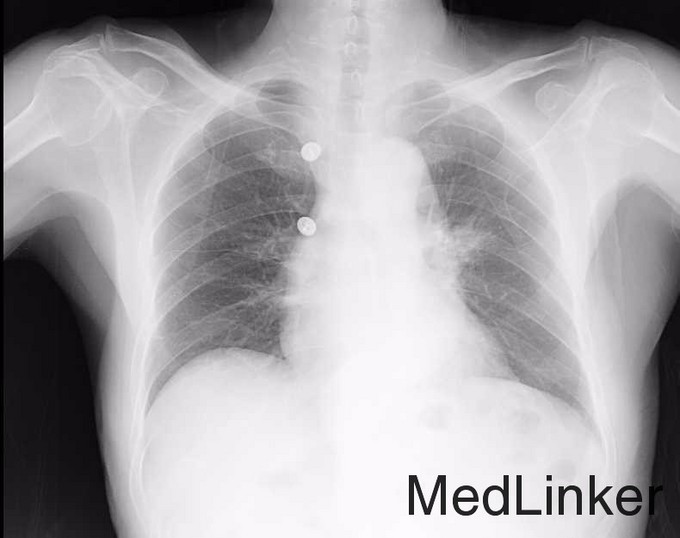

患者男,86岁,主因“咳痰、咳血1月,体检发现肺部病变7月。”以“肺占位性病变 ”收入院。 咳痰、咳血1月,痰量大约2ml,不伴发热、喘憋,2015年10月01日于本院行CT检查:左肺上叶结节,伴周围肺内多发炎性病变,不除外肿瘤性病变可能;右侧斜裂小结节。随为进一步治疗入院

胸部CT: 左肺上叶结节,伴周围肺内多发炎性病变,不除外肿瘤性病变可能;右侧斜裂小结节。